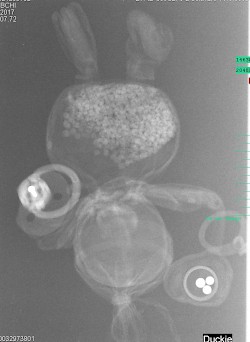

Erst das Kuscheltier - dann das Kind

Kinder kommen oft sehr ängstlich mit Kuscheltieren oder Puppen zum Röntgen. Um den Kindern diese Angst zu nehmen, kann man vor deren neugierigen Augen, zuerst die kuscheligen Begleiter unter die Röhre legen.

Spätestens wenn die Kinder die Bilder Ihrer Kuscheltiere sehen ist die Angst vorm Röntgen meist vergessen. So wie bei den unten abgebildeten Bildern.